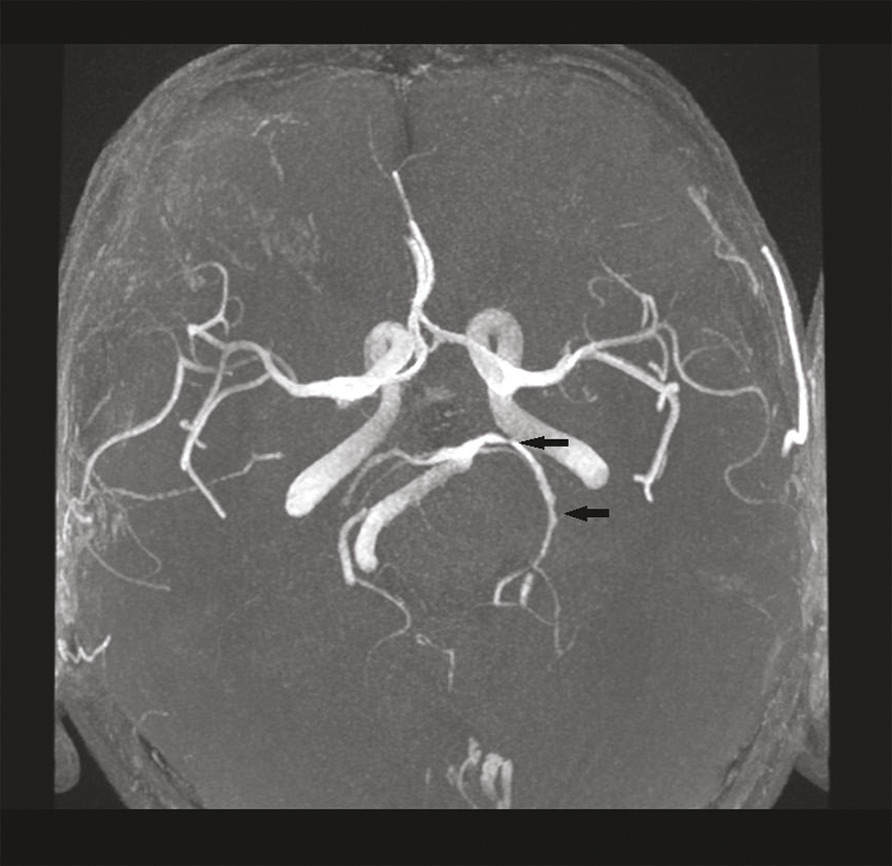

Cet homme de 71 ans est hospitalisé en mars 2020 pour un accident vasculaire cérébral ischémique (AVCi) de la capsule interne gauche (fig. 1 ) d’évolution favorable. L’enquête étiologique est négative mais des causes cardiovasculaires sont considérées comme probables. Après un épisode de céphalées intenses, mal calmées par le paracétamol, le patient est réhospitalisé en urgence début juillet pour une hémiplégie gauche ; l’imagerie révèle un aspect de vascularite cérébrale des gros troncs (fig. 2 ). La maladie de Horton est éliminée. Mi-juillet, un nouvel AVCi se traduit par une aggravation de l’hémiplégie gauche, une confusion mentale, une ataxie. Des échanges téléphoniques et écrits orientent alors vers le diagnostic de borréliose ; la ponction lombaire (95 % de lymphocytes, 8 hématies, protéinorachie 0,93 g/L, IgG anti Borrelia Burgdorferi > 240 UA/mL) et le profil sérologique de la maladie de Lyme (IgG 352 et IgM 2,3 UA/mL en faveur d’une infection semi-récente) confirment la neuro-borréliose active tardive (index de sécrétion intrathécale de 3,3 donc > 2) sous forme d’une méningo-vascularite.1 Un traitement par doxycycline est débuté puis le patient est pris en charge par un service de rééducation fonctionnelle dédié, avec d’importantes séquelles.